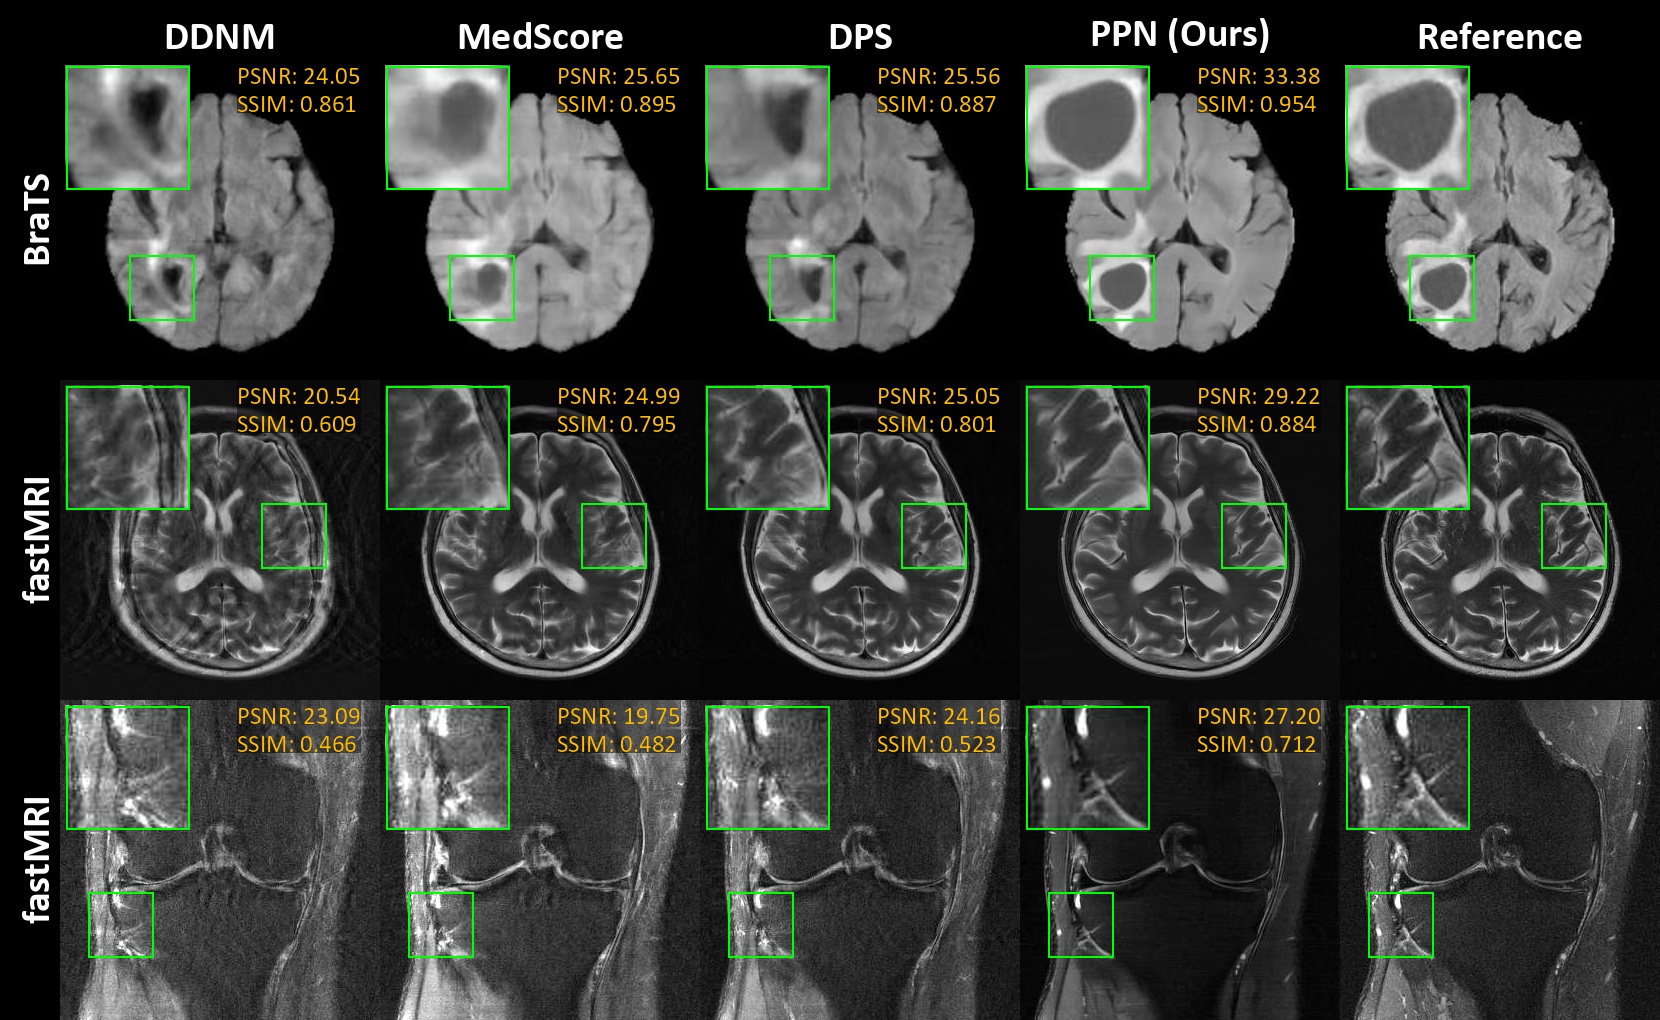

Fig. 2: MRI reconstructions for BraTS [16, 17] and fastMRI knee and brain [18] at 8× acceleration, 50 NFEs.

Figure 2 illustrates the reconstructions of various anatomies at 8x acceleration across all methods, showcasing PPN’s fidelity to the ground truth. In Table 1, PPN is compared with baseline methods for MRI undersampling at 4x, 8x, and 12x accelerations using 50 NFEs. Here, PPN outperforms the baseline methods at all accelerations except for the PSNR metric of the 12x acceleration, showcasing PPN’s generalizability. This superiority is further supported by Table 2, where PPN achieves the highest SSIM for fastMRI knee and brain datasets at 50 NFEs and 8x acceleration. Additionally, Figure 3 shows PPN’s performance against NFEs in PSNR and SSIM at 4x acceleration. Notably, PPN achieves better results with 50 NFEs compared to others at 500 NFEs.